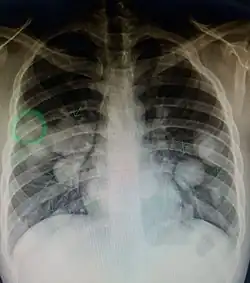

CT image of a lung metastasis -

Metastatic cancer in the lungs -